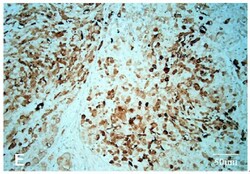

- Main image

- Experimental details

- Figure from citation: Immunohistochemistry of protein level by using anti-ALK antibody in human right cervical lymph node. Dilution: 1:200 View Citation